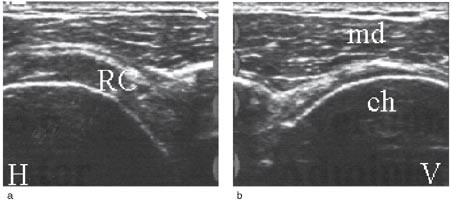

Rotatorcuffrupturer klassifiseres med ultralyd ut fra lokalisasjon, størrelse og grad (partiell, full tykkelse). Hovedlokalisasjonen er distalt i supraspinatussenen ved festet mot tuberculum majus (1). Det er beskrevet tre hoved- og tre tilleggskriterier for ultralydfunn ved cuffrupturer (3, 5). Hovedkriteriene har størst betydning og det kreves påvisning av minst ett av hovedkriteriene i to plan for ultralyddiagnosen rotatorcuffruptur. Sammen med et hovedkriterium støtter hvert av tilleggskriteriene sannsynligheten for diagnosen. Hovedkriteriene er hypoekkoisk defekt (fig 7), tap av konveksitet (fig 8 a, b) og skallet humerushode (fig 9a, b). Hypoekkoisk defekt er typisk for akutte rupturer og representerer en væskeansamling i defekten mellom rupturkantene (1). Tap av konveksitet og skallet humerushode er stadier i en progredierende degenerativ prosess med gradvis skade og retraksjon av rupturendene og herniering av bursavev og deltoidmuskel i defekten.

De tre tilleggskriteriene er den markerte fremstillingen av brusklaget i bunnen av cuffdefekten (double cortex sign) (fig 7), overflateforandringer på tuberculum majus (fig 8b) og væskeansamling i leddet og/eller bursa (fig 10a, b). Forandringene på tuberculum majus er følge av en mikrotraumatisering mellom den nakne beinoverflaten og acromion. Væskeansamling i leddet er best synlig i seneskjeden rundt det lange bicepshodet som hypoekkoisk halo, eller ved utposning av bakre leddkapsel (2, 6). Hollister og medarbeidere (7) fant en positiv prediktiv verdi for rotatorcuffruptur på 60 % ved væske i leddet, 70 % ved væske i bursa og 95 % ved væske begge steder, verifisert ved operasjon.